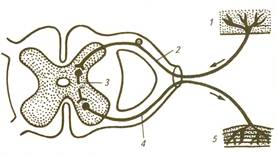

Спинномозговая рефлекторная дуга

Рефлекторная дуга – совокупность структур

организма участвующих в рефлексе, путь, по которому раздражение (сигнал) от

рецептора проходит к исполнительному органу. Рефлекторная дуга включает

рецепторы (1), центростремительные (афферентные) волокна (2); нервный центр

(3); центробежные (эфферентные) волокна (4); исполнительный орган (мышца,

железа и др. – 5). Простейшие рефлексы реализуются спинным мозгом без участия

головного мозга.

В состав спинномозговой рефлекторной дуги

обязательно входят чувствительные и двигательные нейроны. Моносинаптические

(двухнейронные) рефлекторные дуги включает только один синапс, а

полисинаптические (многонейронные) имеют один или несколько вставочных нейронов

и, следовательно, включают по меньшей мере два синапса, находящиеся в ЦНС. Как

правило полисинаптическая спинномозговая рефлекторная дуга формируется

нейронами расположенными в нескольких ядрах и сегментах спинного мозга,

объединенных функционально.

Кроме двигательных рефлекторных дуг,

представленных во всех отделах спинного мозга, на уровне грудного и крестцового

отделов замыкаются вегетативные рефлекторные дуги, осуществляющие контроль

нервной системы за деятельностью внутренних органов.